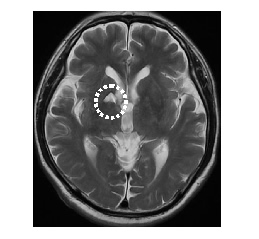

MRI画像

脳梗塞